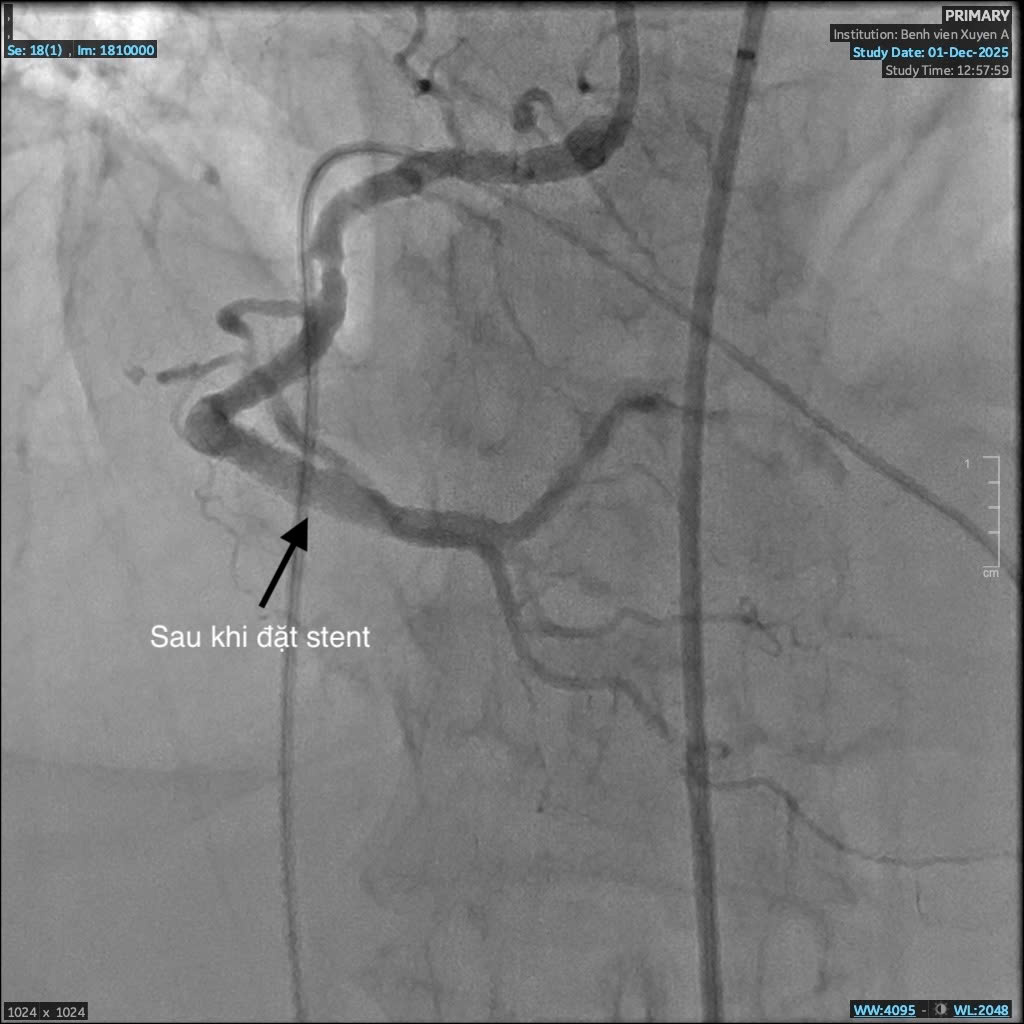

Mạch máu sau khi đặt stent

Sau can thiệp stent, tái thông được mạch máu

Sau can thiệp, tình trạng huyết động của bệnh nhân dần ổn định, triệu chứng khó thở giảm rõ rệt, người bệnh qua cơn nguy kịch. Bệnh nhân tiếp tục được theo dõi sát và điều trị tích cực tại khoa Can Thiệp Tim Mạch, kết hợp kiểm soát các bệnh lý nền như tăng huyết áp, đái tháo đường và suy thận.

BS. Giản Tư Trí – khoa Can Thiệp Tim Mạch BVĐK Xuyên Á cho biết: “Bệnh nhân C. có tiền căn hen phế quản vào viện trong tình trạng suy hô hấp, việc chẩn đoán gặp nhiều khó khăn. Trong quá trình can thiệp, dưới hướng dẫn của hệ thống số hóa xóa nền DSA, ê-kíp nhận thấy mạch vành của bệnh nhân bị vôi hóa nhiều do đái tháo đường, suy thận lâu năm. Vôi hóa là “kẻ thù” của can thiệp mạch vành, gây khó khăn cho việc nong và đặt stent, thậm chí khiến việc can thiệp thất bại. Nhưng với sự tỉ mỉ và kinh nghiệm xử trí nhiều ca đặt stent phức tạp trước đó, các bác sĩ khoa Can Thiệp Tim Mạch đã vượt qua thách thức và đặt stent thành công, tái thông mạch máu nuôi tim, cứu bà C. qua cơn nguy kịch.”